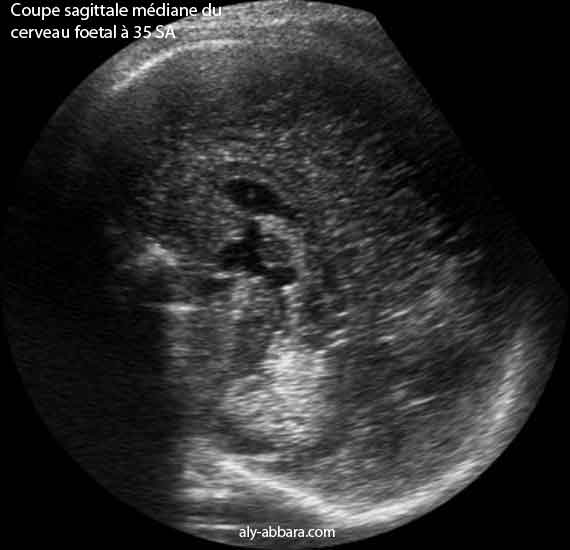

Coupe sagittale médiane puis coronale du cerveau fœtal à 35 SA permettant la mise en évidence :

• la coupe sagittale médiane : corps calleux, le fornix, le cavum du septum lucidum, le cavum vergae, le troisième ventricule, l'aqueduc de Sylvius, le quatrième ventricule.